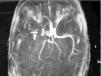

Ante los hallazgos clínicos, a los 3 días de vida se realiza resonancia magnética (RM) cerebral, apreciándose un extenso infarto agudo dependiente de la arteria cerebral media derecha (fig. 1). El EEG y la ecografía cerebral realizadas a los 5 días, mostraron, respectivamente, presencia de ondas agudas frontales derechas ocasionales y un aumento de ecogenicidad en la región parietal, temporal derecha y tálamo derecho. Se completó el estudio con una ecografía Doppler cerebral y una angio-RM (fig. 2) que objetivaron ausencia de flujo en arteria cerebral media derecha confirmando el diagnóstico de infarto cerebral.

Figura 2. Angio-RM: ausencia de ACM derecha.